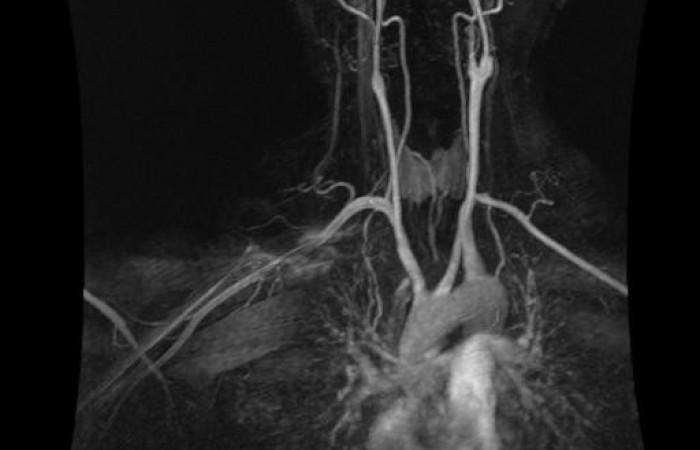

ˇ angiografia bez środków kontrastowych

ˇ angiografia z podaniem środków kontrastowych (ze strzykawki automatycznej)

ˇ angiografia obwodowa z podaniem środka kontrastowego (strzykawka automatyczna, automatyczny przesuw stołu)

ˇ angiografia obwodowa bez podania środka kontrastowego

Pracownia została założona w roku 1977 jako pierwsza w regionie Polski Południowo-Wschodniej. Wyposażona jest w nowoczesny cyfrowy angiograf, pracujący w systemie subtrakcji cyfrowej (DSA). Możliwe jest wykonywanie na nim tzw. badań rotacyjnych dzięki, którym otrzymujemy trójwymiarową rekonstrukcję obrazów, szczególnie przydatną przy ocenie malformacji naczyniowych. Akwizycja obrazów wykonywana jest przy pomocy tzw. płaskiego, cyfrowego panelu obrazowego. Dodatkowa opcja tzw. DynaCT pozwala na wykonywanie badań, których obrazy są zbliżone do tych uzyskiwanych w tomografii komputerowej. Umożliwia to na jednoczasowe uzyskiwanie dodatkowych informacji o operowanej zmianie bez konieczności przenoszenia chorego pacjenta do Pracowni Tomografii Komputerowej. Ponadto system wyposażony jest w dodatkową stację komputerową służącą do zaawansowanej obróbki danych obrazowych.

- pełny zakres badań diagnostycznych (angiografii), za wyjątkiem badań naczyń wieńcowych;